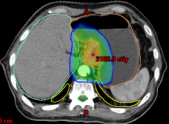

病例展示三:胰腺癌

腺癌病灶压迫并侵润十二指肠,十二指肠梗阻不能正常进食,患者留置营养管及胃肠减压管;伴胆道梗阻诱发黄疸,留置PTCD引流管。诊断:1.胰头恶性肿瘤 cT4N0M0 III期 KPS评分:80分;2.十二指肠不全梗阻;3.梗阻性黄疸,4.心律失常 室性期前收缩5. 慢性心力衰竭6.陈旧性心肌梗死7.冠状动脉粥样硬化性心脏病8. 缺血性心肌病。治疗:2024-05月开始吉西他滨+白蛋白紫杉醇化疗4周期,碳离子放疗剂量:PTV 36Gy(RBE)/9fx,后缩野补量,剂量:PTV boost 18Gy(RBE)/4fx,4.5Gy(RBE)/fx。

疗效评价